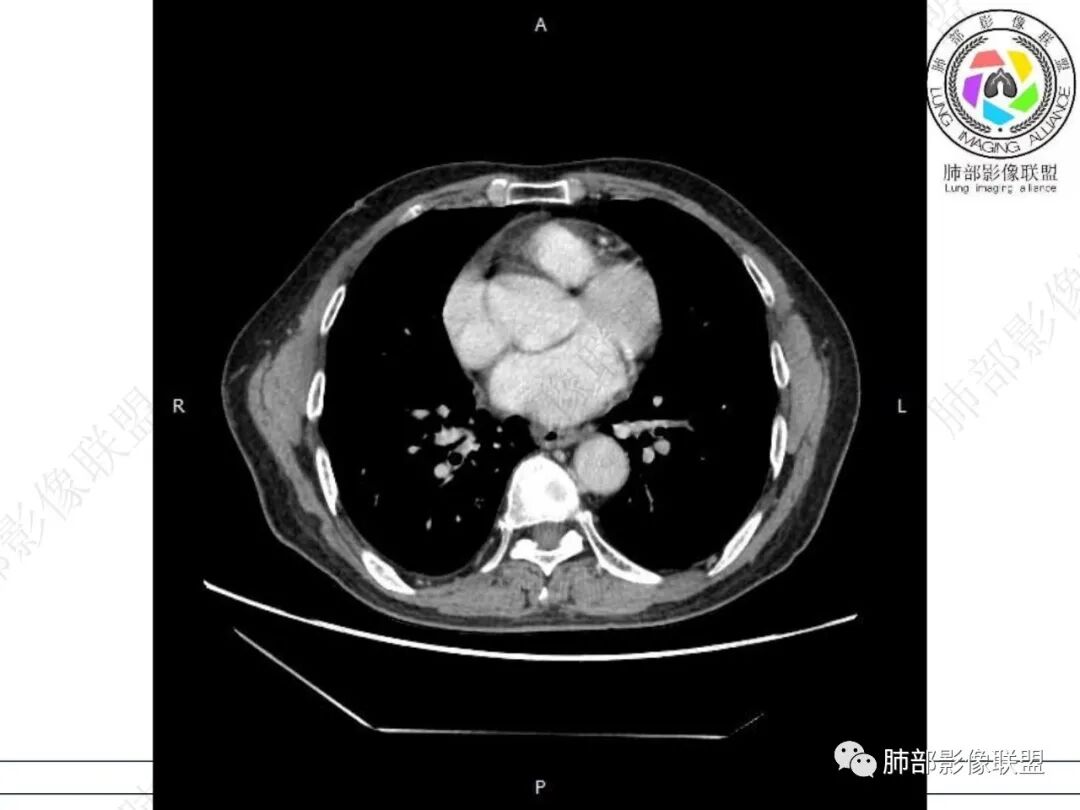

气管隆突下团片影,其内积气,与食道分界不清,食道壁增厚,管腔狭窄,右下肺实变影,支气管壁增厚,考虑食管支气管瘘并右下肺感染,食道肿瘤病变不除外

支持食管支气管瘘(考虑食管癌)伴后纵隔及右肺感染,食管管壁明显增厚,管腔狭窄,相邻右侧后纵隔内软组织内可见气体影,与食管分界不清,右肺有实变及不张。

右肺下叶背段条片状实变影,内可见支气管走行,支气管有狭窄有扩张,周围可见磨玻璃影,隆突下团片影,内密度不均可见气体影,与周围结构界限不清。食管下段壁增厚,管腔狭窄,右肺下叶慢性炎、肺不张,考虑食道肿瘤所致气管食管瘘。

老年男性,慢性病程,右肺下叶斑片影、斑点影、实变影,支气管轻度扩张,病灶整体稍收缩;食道壁增厚、肿胀、模糊,气管隆突及右后纵隔旁见软组织块影,其内见气泡影,均匀强化,符合食道支气管瘘伴周围炎症,右下肺炎症

右肺下叶沿肺叶肺段分布斑片、条片状影,以下叶背段为显,边缘模糊,内可见支气管走行,局部支气管管壁增厚,右侧胸腔少量积液。纵隔隆突下可见不均匀软组织密度影,与周围结构分界不清,内见气体密度影,与食管及相邻右肺支气管之间未显示通道。邻近食管下段壁明显不规则增厚,增强后食管管壁明显不均匀强化,可见线样强化的连续完整粘膜影。